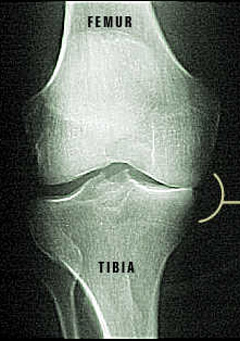

X-ray of Damaged Knee Joint

Damaged Knee

Notice how the femur is rubbing against the tibia.  That is because the cartilage on top of the tibia has been damaged.  Since only one side is affected, a partial knee surgery is possible.